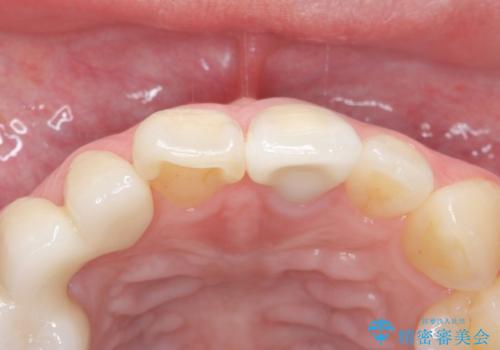

歯ぐきの状態も良く、適合の良い被せ物を入れることができました。

審美性もかなり改善され、大変喜んでいただけました。